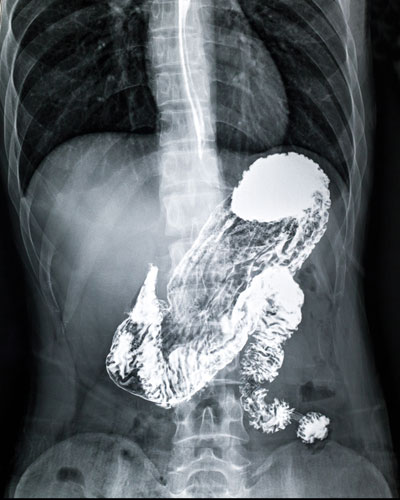

For the upper gastrointestinal study it is called barium meal or barium meal with follow through if it is required to visualize the small intestines. For the lower gastrointestinal study, it is called barium enema.

For barium meal: to observe digestive function or to detect abnormalities such as ulcers, tumours or inflammation of the oesophagus, stomach and duodenum.

Barium meal

You will be asked to step on the pedestal of the x-ray machine.

Then you will be asked to drink a cup of liquid barium, which resembles a white-coloured milkshake, with a chalky taste.

The radiologist and/or the diagnostic radiographer will note the passage of barium into your oesophagus and stomach on the fluoroscopic monitor.

The table will then be moved to a horizontal position and you will then be lying down as the radiologist and/or the diagnostic radiographer obtains pictures of your oesophagus, stomach and duodenum.

You will be asked to hold your breath to prevent blurring of the still images. Also, periodically you will be asked to move into different positions while standing and to roll into different positions while lying on the examining table.

The examination is usually completed within 20 minutes.

If a follow through is required you will be asked to wait from about 30 minutes to a few hours to follow the passage of barium through your intestines. X-rays of your abdomen will be periodically taken.